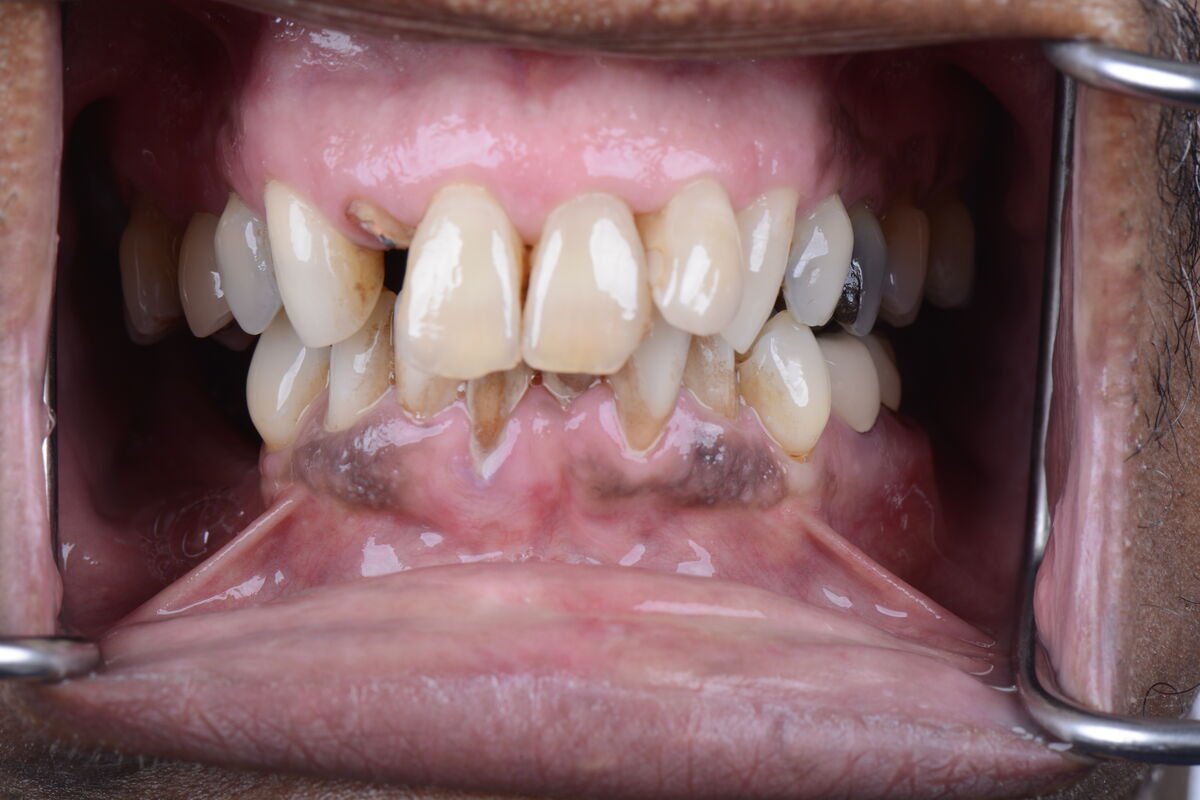

Real Smile Transformations

See the life-changing results from real patients who chose Fusion Dental Implants.

Our practice is built around the full arch restoration, including All-on-4, All-on-6, and zygomatic implant procedures. These treatments replace an entire arch of missing or failing teeth with a fixed, permanent set of new teeth supported by as few as four dental implants. Many of our patients receive temporary teeth on the same day as their surgery, leaving our office with a complete smile.

Our board-certified oral and maxillofacial surgeons bring fellowship training in complex implant reconstruction, meaning we routinely treat patients who have been told they are not candidates for implants elsewhere. Whether the challenge involves severe bone loss, prior implant failure, or complex medical history, our team has the training and technology to find a solution tailored to each patient.